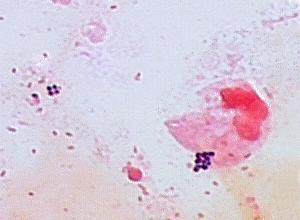

This Gram stain of a male urethral discharge is suggestive of...